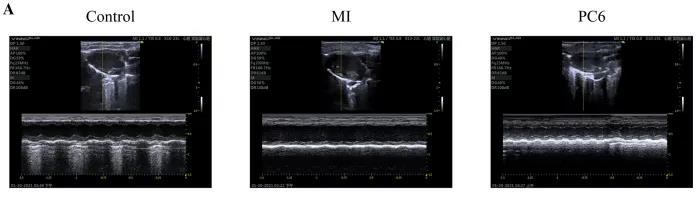

為了探討針刺PC6穴對心肌損傷的影響,作者首先評估了心功能和梗死面積。超聲心動圖結(jié)果顯示MI組的EF(ejection fraction)和FS(fractional shortening)均較對照組明顯降低。PC6穴位治療后,EF和FS均增加。針刺治療5天后, 采用TTC染色檢測梗死面積。結(jié)果顯示,針刺治療顯著減小心肌損傷的大小。采用ELISA法測定反映急性心肌損傷的心肌特異性血清酶,包括心肌肌鈣蛋白T (cTnT)和心肌肌鈣蛋白I (cTnI)的水平。結(jié)果表明,心肌梗死術后cTnT和cTnI水平升高,針刺可顯著降低血清酶水平。